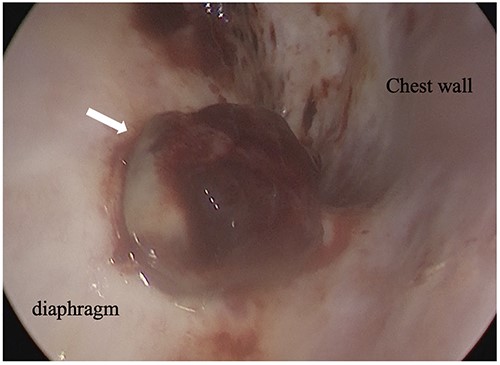

An 81-year-old man who underwent surgical resection for lung cancer 2 years previously was referred for the examination of a right diaphragmatic mass that was pointed out during follow-up. Computed tomography (CT) revealed pleural effusion and two contrast-enhanced nodules (17 × 10 and 10 × 10 mm) in the right diaphragm (Fig. 1A); however, he had no symptoms. Positron emission tomography (PET)/CT was performed, but no FDG accumulation was found (Fig. 1B). Although hemangioma was suspected based on the preoperative imaging, we were unable to exclude the recurrence of lung cancer. Therefore, the patient was admitted for the examination of the right diaphragmatic nodules by VATS. A 4-cm thoracotomy wound was created at the 8th intercostal mid-axillary line, and a 5.5-mm port was created at the 6th intercostal anterior axillary line. Observation of the thoracic cavity revealed reddish brown pleural effusion and two large and small pedunculated tumors on the diaphragm (Fig. 2). The smaller nodule spontaneously fell off during the process of cleaning the thoracic cavity and was submitted for a rapid intraoperative diagnosis. As hemangiomas were diagnosed during the operation, the roots of the smaller nodule and the larger nodule that fell off were treated using an ultrasonic coagulation and incision device while partially leaving the abdominal layer of the diaphragm. Partial excision was performed (Fig. 3). The nodules were 1.7 × 1.7 and 1.5 × 1.5 cm with a brown surface (Fig. 4). Histopathologically, the nodules were mostly blood clots, and a collection of thin-walled blood vessels with red blood cells was observed (Fig. 5A). An immunohistochemical analysis revealed that the vascular endothelial cells were positive for CD31 and CD34 (Fig. 5B). Thus, the nodules were diagnosed as diaphragmatic hemangioma. No hemangiomatous lesions were noted in the normal connective tissue in the additional resected tissue specimens (Fig. 6). The postoperative course was normal, and the patient is being followed up in an outpatient setting. It has been 16 months since the operation, but no recurrence has been observed at this time.

Intraoperative thoracoscopic image, and two consecutive reddish, smooth nodules were observed on the surface of the diaphragm.